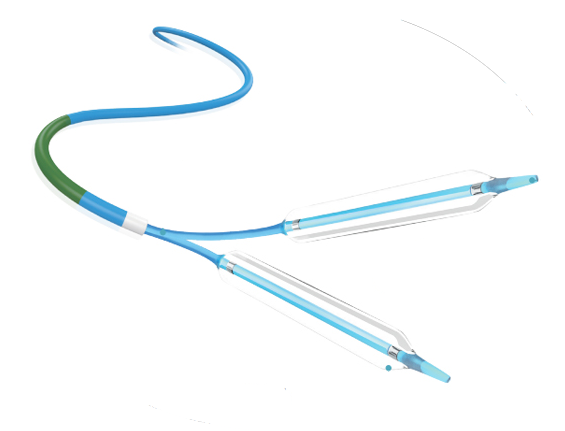

Tadpole™

Coronary Dilation Catheter

Coronary Dilation Catheter

Tadpole™ and Mini Tadpole™ models. Available in Compliant and Semi-Compliant versions.

CORONARY DILATATION CATHETER

Tadpole ™ & MiniTadpole ™

This catheter is a kind of rapid exchange catheter with an integrated shaft system and a balloon near the distal tip. The balloon has two radiopaque markers to aid in positioning the balloon in the stenosis, and is designed to provide an expandable segment of known diameter and length at a specific pressure.

0.017" SOFT TAPERED TIP

SHORT AND ROUND SHOULDER DESIGN

HYDROSURF ™ COATING ON DISTAL SHAFT

PEBAX BALLON MATERIAL

GREAT RE-FOLDING ABILITY

AVAILABLE: COMPLIANT AND SEMI-COMPLIANT